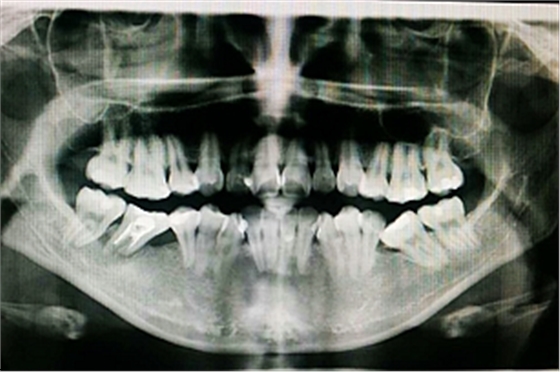

首頁(yè)病案整理(群) 群病例整理(正畸)

群病例整理(正畸)

2017年03月23日23:00